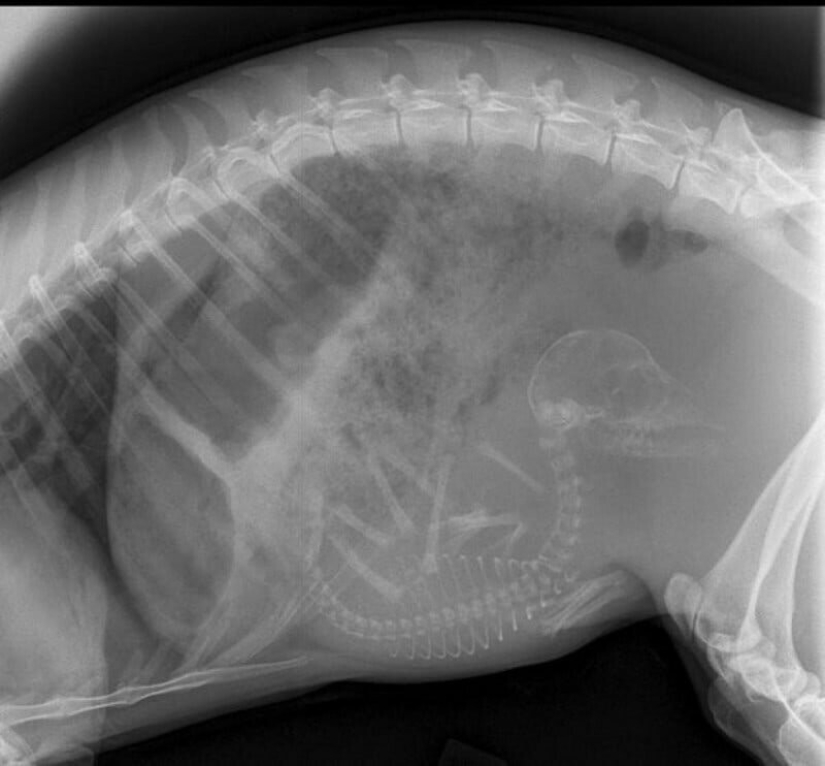

Conejillo de Indias embarazada